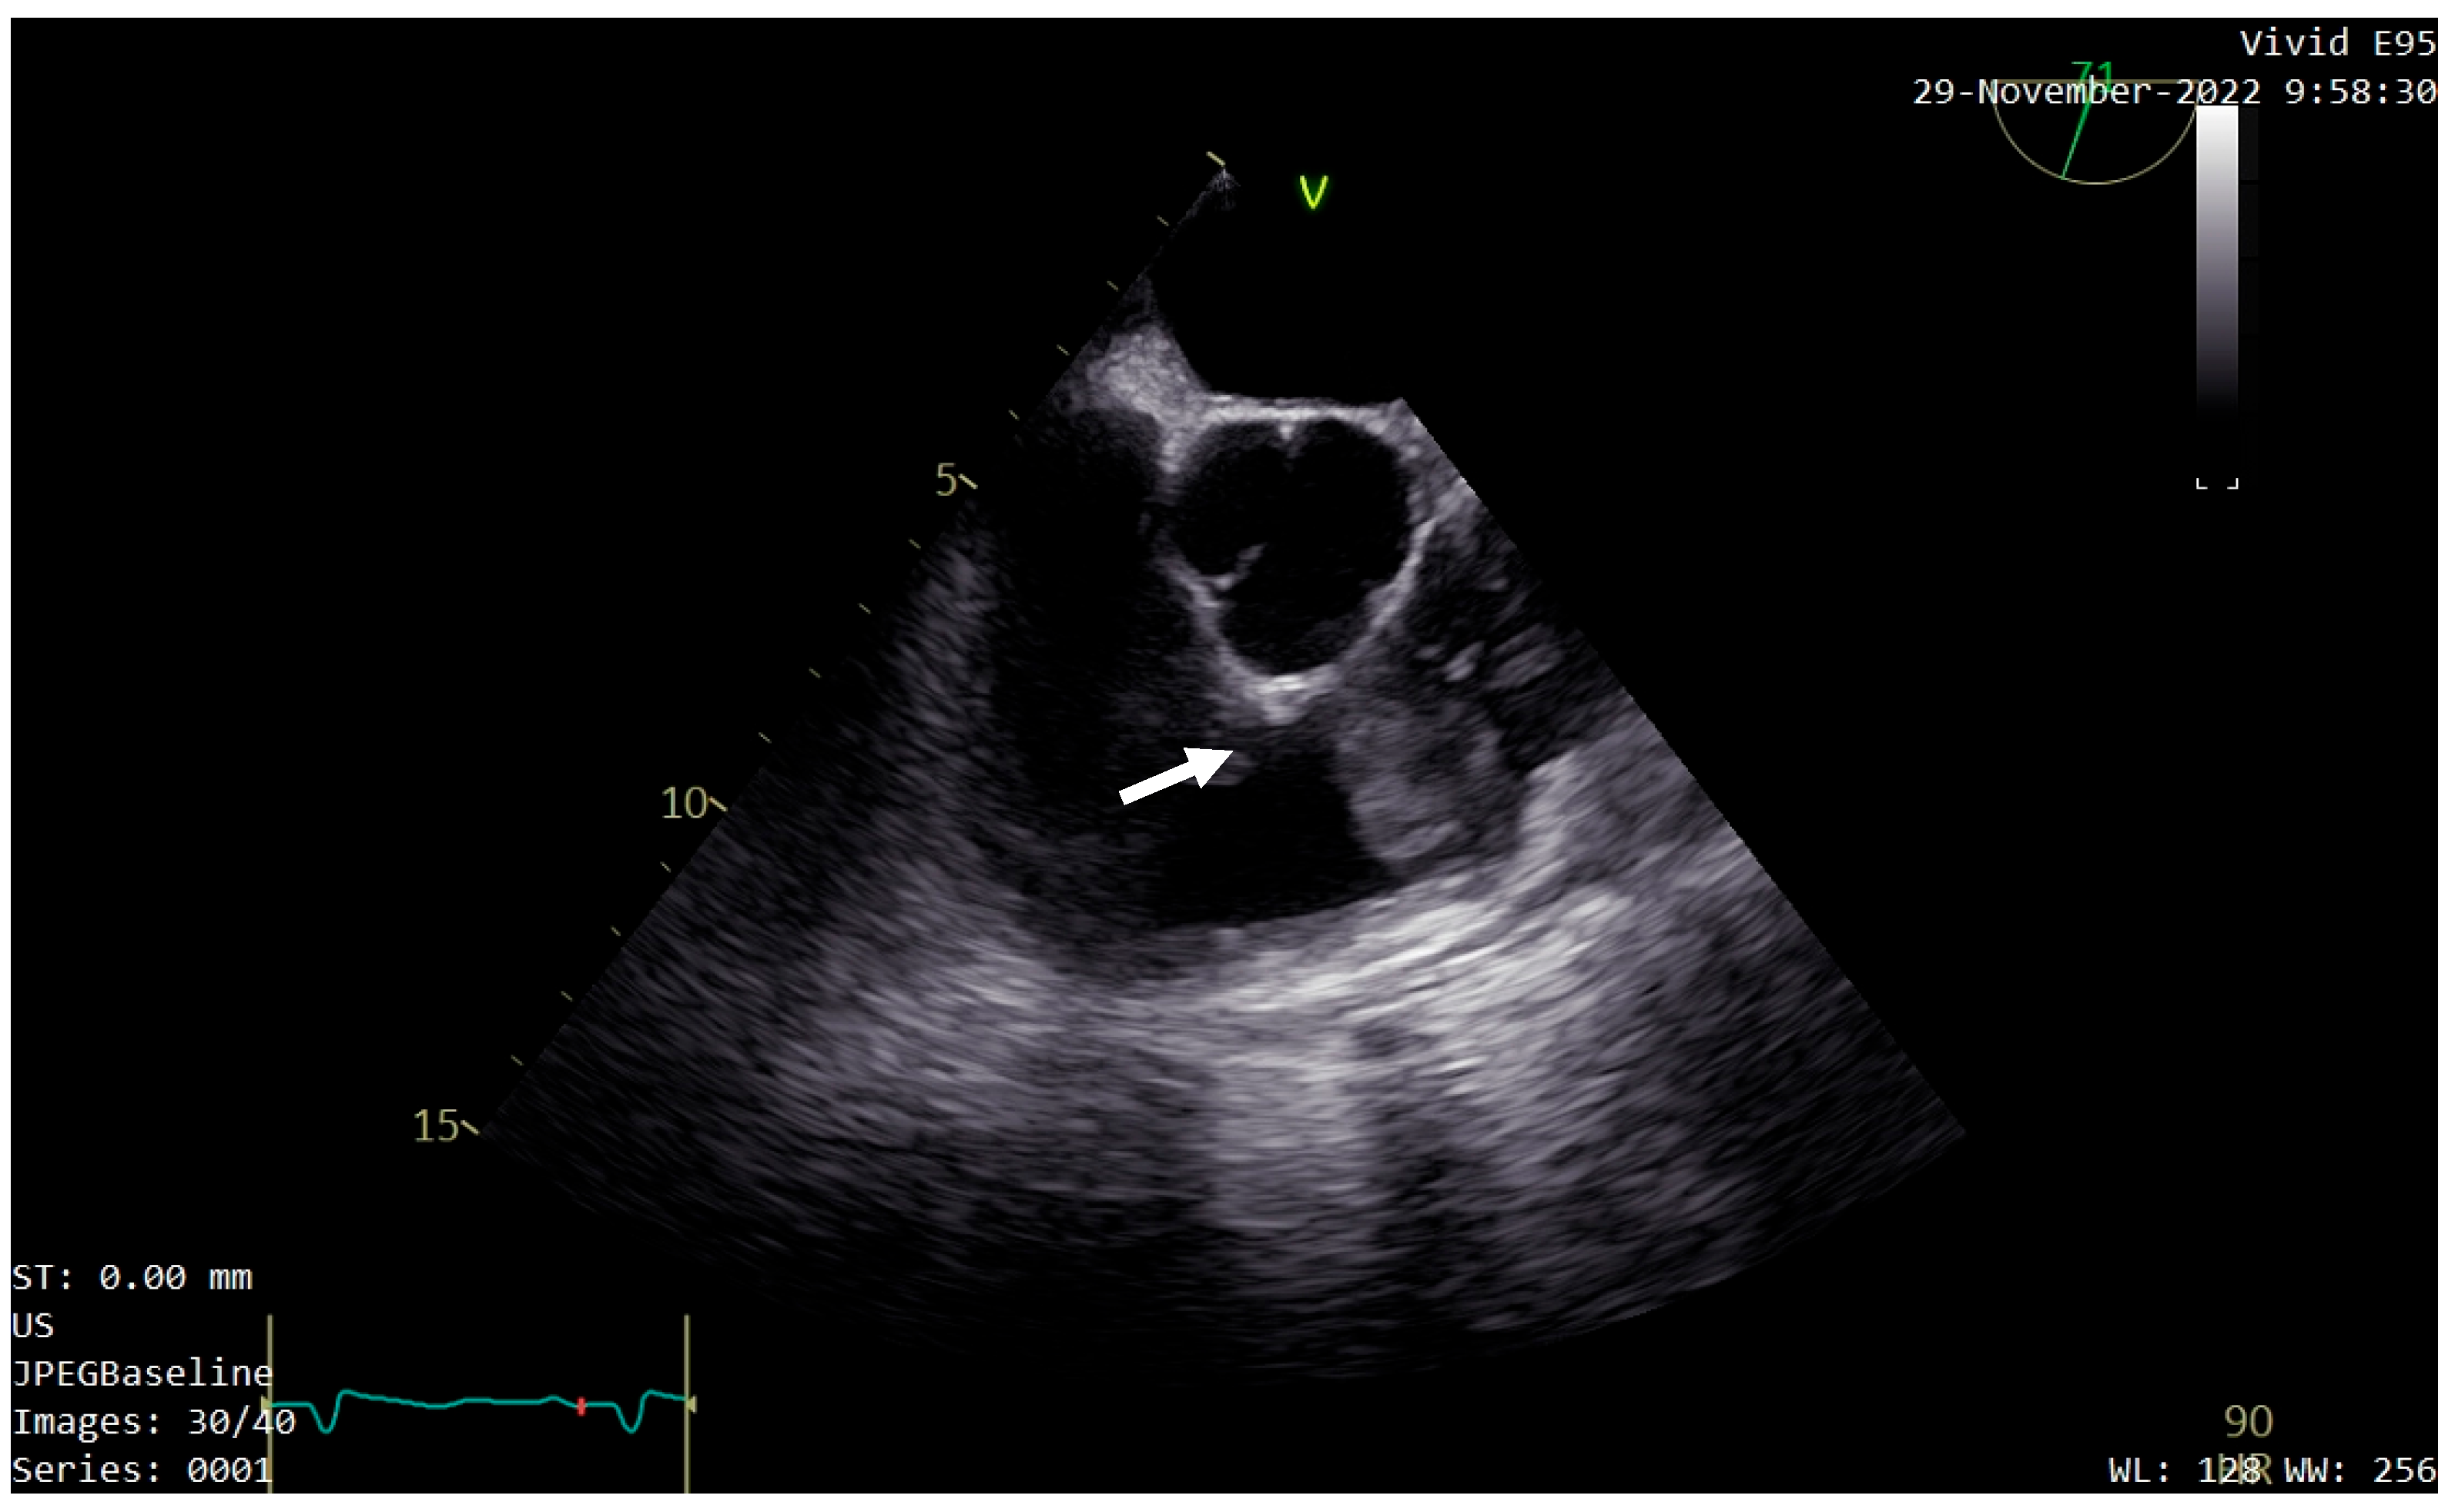

For a better evaluation of the tumor, transesophageal echocardiography (TEE) was performed. It confirmed the location, size, and shape of the tumor, describing it as having low echogenicity, with a similar texture to the myocardium (Figure 3). Comparable pressure gradients at the pulmonary valve were recorded, and patent foramen ovale was identified.

Figure 3. Transesophageal echocardiography (TEE) confirming the location, size, and shape of the tumor (white arrow).